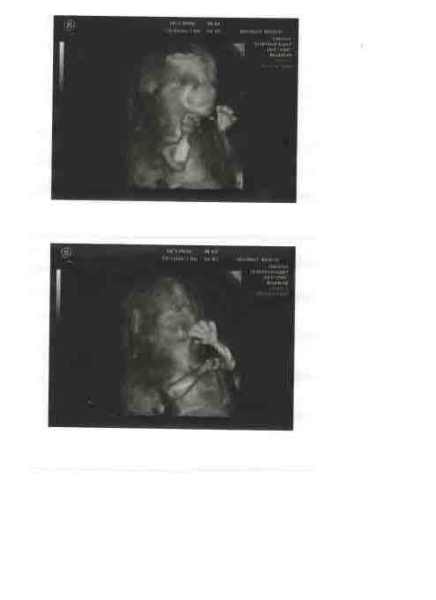

Én holnap megyek uh-ra! Du 4-re!